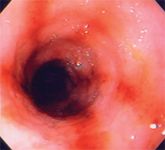

More veterinary hospitals are now incorporating endoscopy equipment in their clinics.

Gastrointestinal (GI) cytology offers many advantages to the small animal practitioner in the assessment of patients with gastrointestinal tract disease.

Esophageal foreign bodies and esophagitis have the potential, if not identified and treated, to cause esophageal strictures or megaesophagus, which can be more difficult to treat.